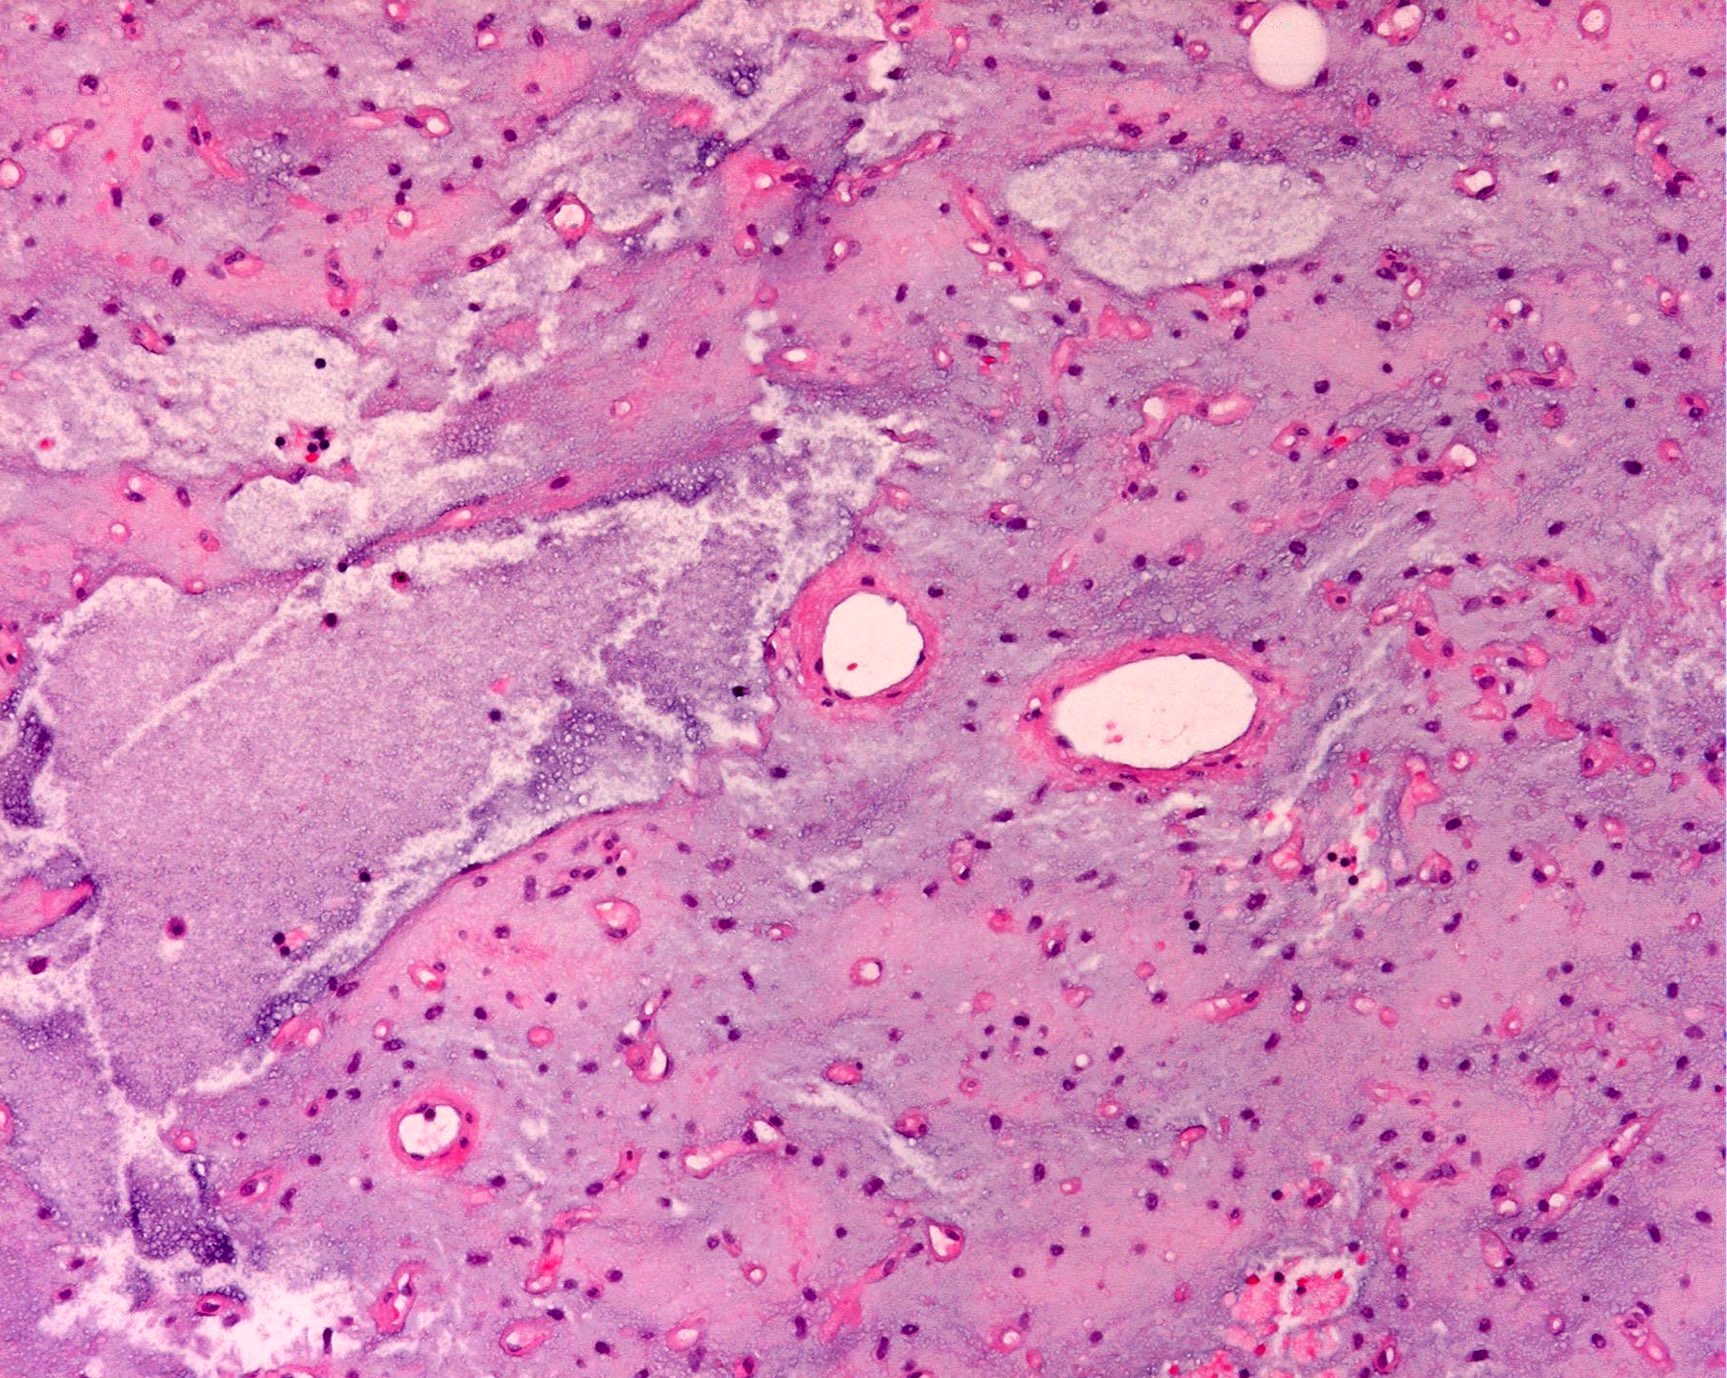

- High grade

- Hypercellular solid sheets of back to back cells with round cell or primitive cytomorphology in > 5% of the sampled tumor

- Cells can have a small amount of hypereosinophilic cytoplasm, a finding of no clinical significance but of significant diagnostic confusion, especially in a limited sample

- Pitfalls and tips

- High grade tumors are so cellular that you can typically walk across nuclei in a high power field without stepping in matrix

- When in doubt, especially in a small sample, pursue molecular testing (typically fluorescent in situ hybridization) for FUS gene rearrangement